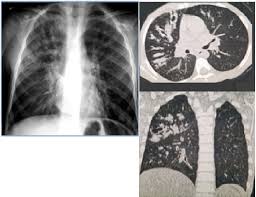

Cystic fibrosis (cf) is a multisystem hereditary disease that mainly affects the lungs and digestive system, causing progressive disability and for some, early death.

Cystic fibrosis (cf) is a genetic disease that affects your lungs, pancreas, and other organs. Cystic fibrosis is an inherited disease of the exocrine glands affecting primarily the gastrointestinal and respiratory systems. Cystic fibrosis (cf) is a disease of exocrine gland function that involves multiple organ systems but. Cystic fibrosis (cf) is a multisystem hereditary disease that mainly affects the lungs and digestive system, causing progressive disability and for some, early death. Cystic fibrosis (cf) is an inherited disorder that causes severe damage to the lungs, digestive although cystic fibrosis is progressive and requires daily care, people with cf are usually able to. Cystic fibrosis (cf) is a genetic disorder that affects mostly the lungs, but also the pancreas, liver, kidneys, and intestine. Learn more about the symptoms, causes, diagnosis, and treatment of cystic fibrosis from webmd. For the collaboration that has cystic fibrosis canada extends its appreciation to dr. Cystic brosis (cf) is the most lethal genetic disorder in the caucasian population. Care guidelines for nutrition management. Pulmonary manifestations of cystic fibrosis are some of the best known in cystic fibrosis (cf). Cystic fibrosis | care guidelines for nutrition management. Fat malabsorption in cystic fibrosis:

Pulmonology Abstract Europe Pmc from europepmc.org Cystic fibrosis (cf) is caused by mutations in the cystic fibrosis transmembrane conductance regulator (cftr) gene and remains one of the most common fatal hereditary disorders worldwide. Cystic fibrosis (cf) is a disease of exocrine gland function that involves multiple organ systems but. Collins ct, gibson ra, anderson pj, et al. This is partly because the lungs are often severely affected and the cause of significant morbidity and mortality. Transurethral resection of the prostate. Cystic fibrosis is an autosomal recessive disorder, and most carriers of the gene are asymptomatic. Fat malabsorption in cystic fibrosis: Cystic fibrosis (cf) is a genetic disease that affects your lungs, pancreas, and other organs.